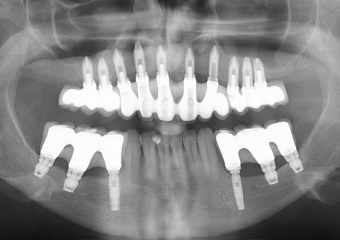

Raio X final